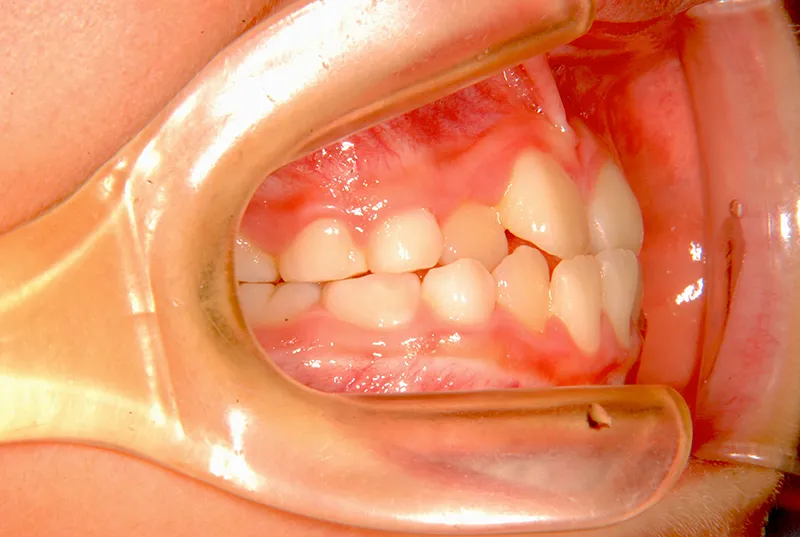

【子供の矯正(一期)】叢生・切端咬合・受け口・永久歯が生える隙間がない・非抜歯症例・8歳男子【K.Y様】

初診時年齢 小学校3年生 (男性) 主訴 前歯の噛み合わせが悪い

診断名 切端咬合 装置名

状態 永久歯が生える隙間がない(叢生)

受け口(下顎前突/反対咬合)

切端咬合

上の歯も下の歯も歯が生えるスペースが少ない為ガタガタしています。

前歯同士が上下で付き合わせる様に噛み(切端咬合)、

その横の歯は上の歯が下の歯の後ろにきて噛んでいる状態です(反対咬合)

初診